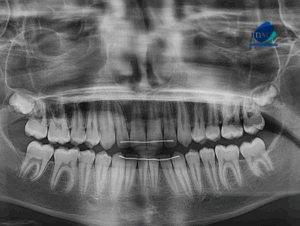

Paciente femenina de 46 años, es referido al Instituto de Diagnóstico Maxilofacial – IDM (Sede Surco) para evaluación general. Radiografia Panorámica En la radiografía panorámica